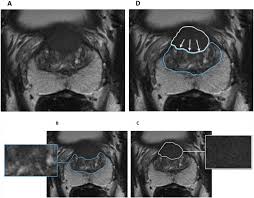

Mri Twice As Likely As Biopsy To Spot Prostate Cancer Research Shows Prostate Cancer The Guardian

Mri Twice As Likely As Biopsy To Spot Prostate Cancer Research Shows Prostate Cancer The Guardian from i.guim.co.uk